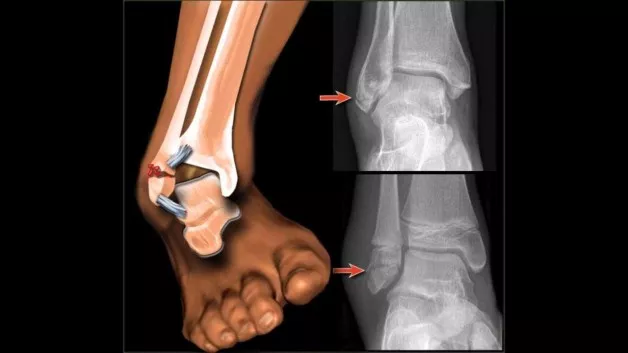

#1 Zvin gležnja

»Do zvina gležnja prihaja pogosto, kljub temu, da se velika večina košarkarjev »bandažira«. Pri zvinu gležnja se lahko poškoduje ena ali več vezi, ki stabilizirajo gleženj. Najpogostejši mehanizem poškodbe je inverzija s kombinacijo plantarne fleksije - stopalo se zvije na notri. Težava je, da košarkarji ne izvajajo dovolj pogosto preventivnih vaj za stabilizacijo gležnja.«